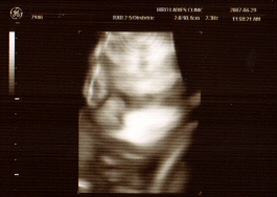

Here is the latest scan of Rikuto, and this time the 4D picture has come out better than the usual ones I post on this blog. Can you see his face? Do you see that highly distinguished nose? He sure takes after his father!

he does, he does!!